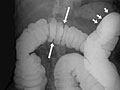

• En un estudio de doble contraste o de contraste con aire, primero se llena el colon de bario y a continuación se drena el bario. Esto deja solo una capa delgada de bario en la pared del colon. El colon entonces se llena con aire. Esto proporciona una visión detallada de la superficie interior del colon. Hace que sea más fácil ver zonas estrechadas (compresiones), divertículos e hinchazón.

El enema de bario, o examen del tubo digestivo inferior, es una radiografía del intestino grueso (colon y recto).

Se detectan uno o varios problemas en el colon, tales como:

• Una sección del colon que no se llenó de bario.

• Un estrechamiento (compresión) en el intestino.

• Pólipos o crecimientos en la pared interior del colon.

• Sacos en la pared del colon ( diverticulosis).

• Problemas con anomalías e inflamación (colitis) del revestimiento del colon.

• Un segmento estrechado o un asa intestinal retorcida que está causando una obstrucción.

• Un intestino plegado en un niño, lo que es señal de invaginación. El enema de bario puede usarse como tratamiento para que el intestino vuelva a su posición normal.